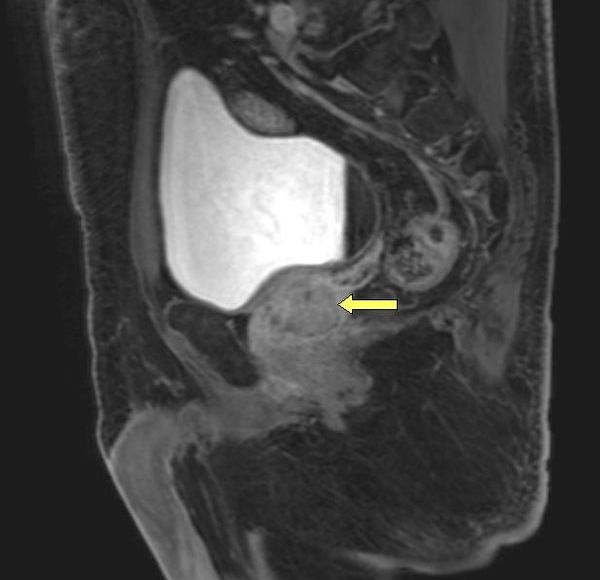

Ryc E - przekrój strzałkowy przez miednicę, gdzie widać pod pęcherzem moczowym gruczoł krokowy. Rozdzielczość MRI pozwala nawet na określenie rozrostu podścieliska, a kolejne opcje w aplikacji umożliwiają zdefiniowanie czy nie ma rozpadów komórek, co sugerowałoby obecność ogniska nowotworowego.

Zdecydowanie lepiej w wykrywaniu gruczolakoraków sprawdza się badanie metodą rezonansu magnetycznego. W przypadku RM nie ma potrzeby umieszczania przedmiotów w odbytnicy, tylko całe badanie odbywa się w bardziej komfortowych warunkach. Radiolog na uzyskanych obrazach nie tylko może zobaczyć zmiany ogniskowe w prostacie, które budzą niepokój, ale także, dzięki wykorzystaniu apletów w postaci spektroskopii może ustalić jaki jest skład błon komórkowych w tej patologicznej zmianie. Jeżeli wzbudza silne podejrzenia rozrostu nowotworowego to należy wykonać biopsję.